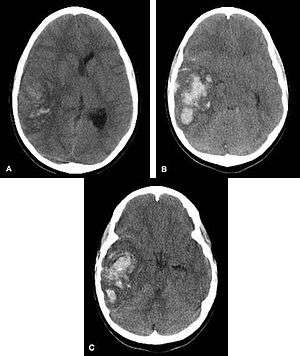

Multiple intraparenchymal hemorrhage

Hemorrhagic neoplasms are more complex, heterogeneous bleeds often with associated edema. These hemorrhages are related to tumor necrosis, vascular invasion and neovascularity. Glioblastomas are the most common primary malignancies to hemorrhage while thyroid, renal cell carcinoma, melanoma, and lung cancer are the most common causes of hemorrhage from metastatic disease.

Nontraumatic intraparenchymal hemorrhage most commonly results from hypertensive damage to blood vessel walls e.g.: - hypertension - eclampsia - drug abuse, but it also may be due to autoregulatory dysfunction with excessive cerebral blood flow e.g.: - reperfusion injury - hemorrhagic transformation - cold exposure - rupture of an aneurysm or arteriovenous malformation (AVM) - arteriopathy (e.g. cerebral amyloid angiopathy, moyamoya) - altered hemostasis (e.g. thrombolysis, anticoagulation, bleeding diathesis) - hemorrhagic necrosis (e.g. tumor, infection) - venous outflow obstruction (e.g. cerebral venous sinus thrombosis). Nonpenetrating and penetrating cranial trauma can also be common causes of intracerebral hemorrhage.